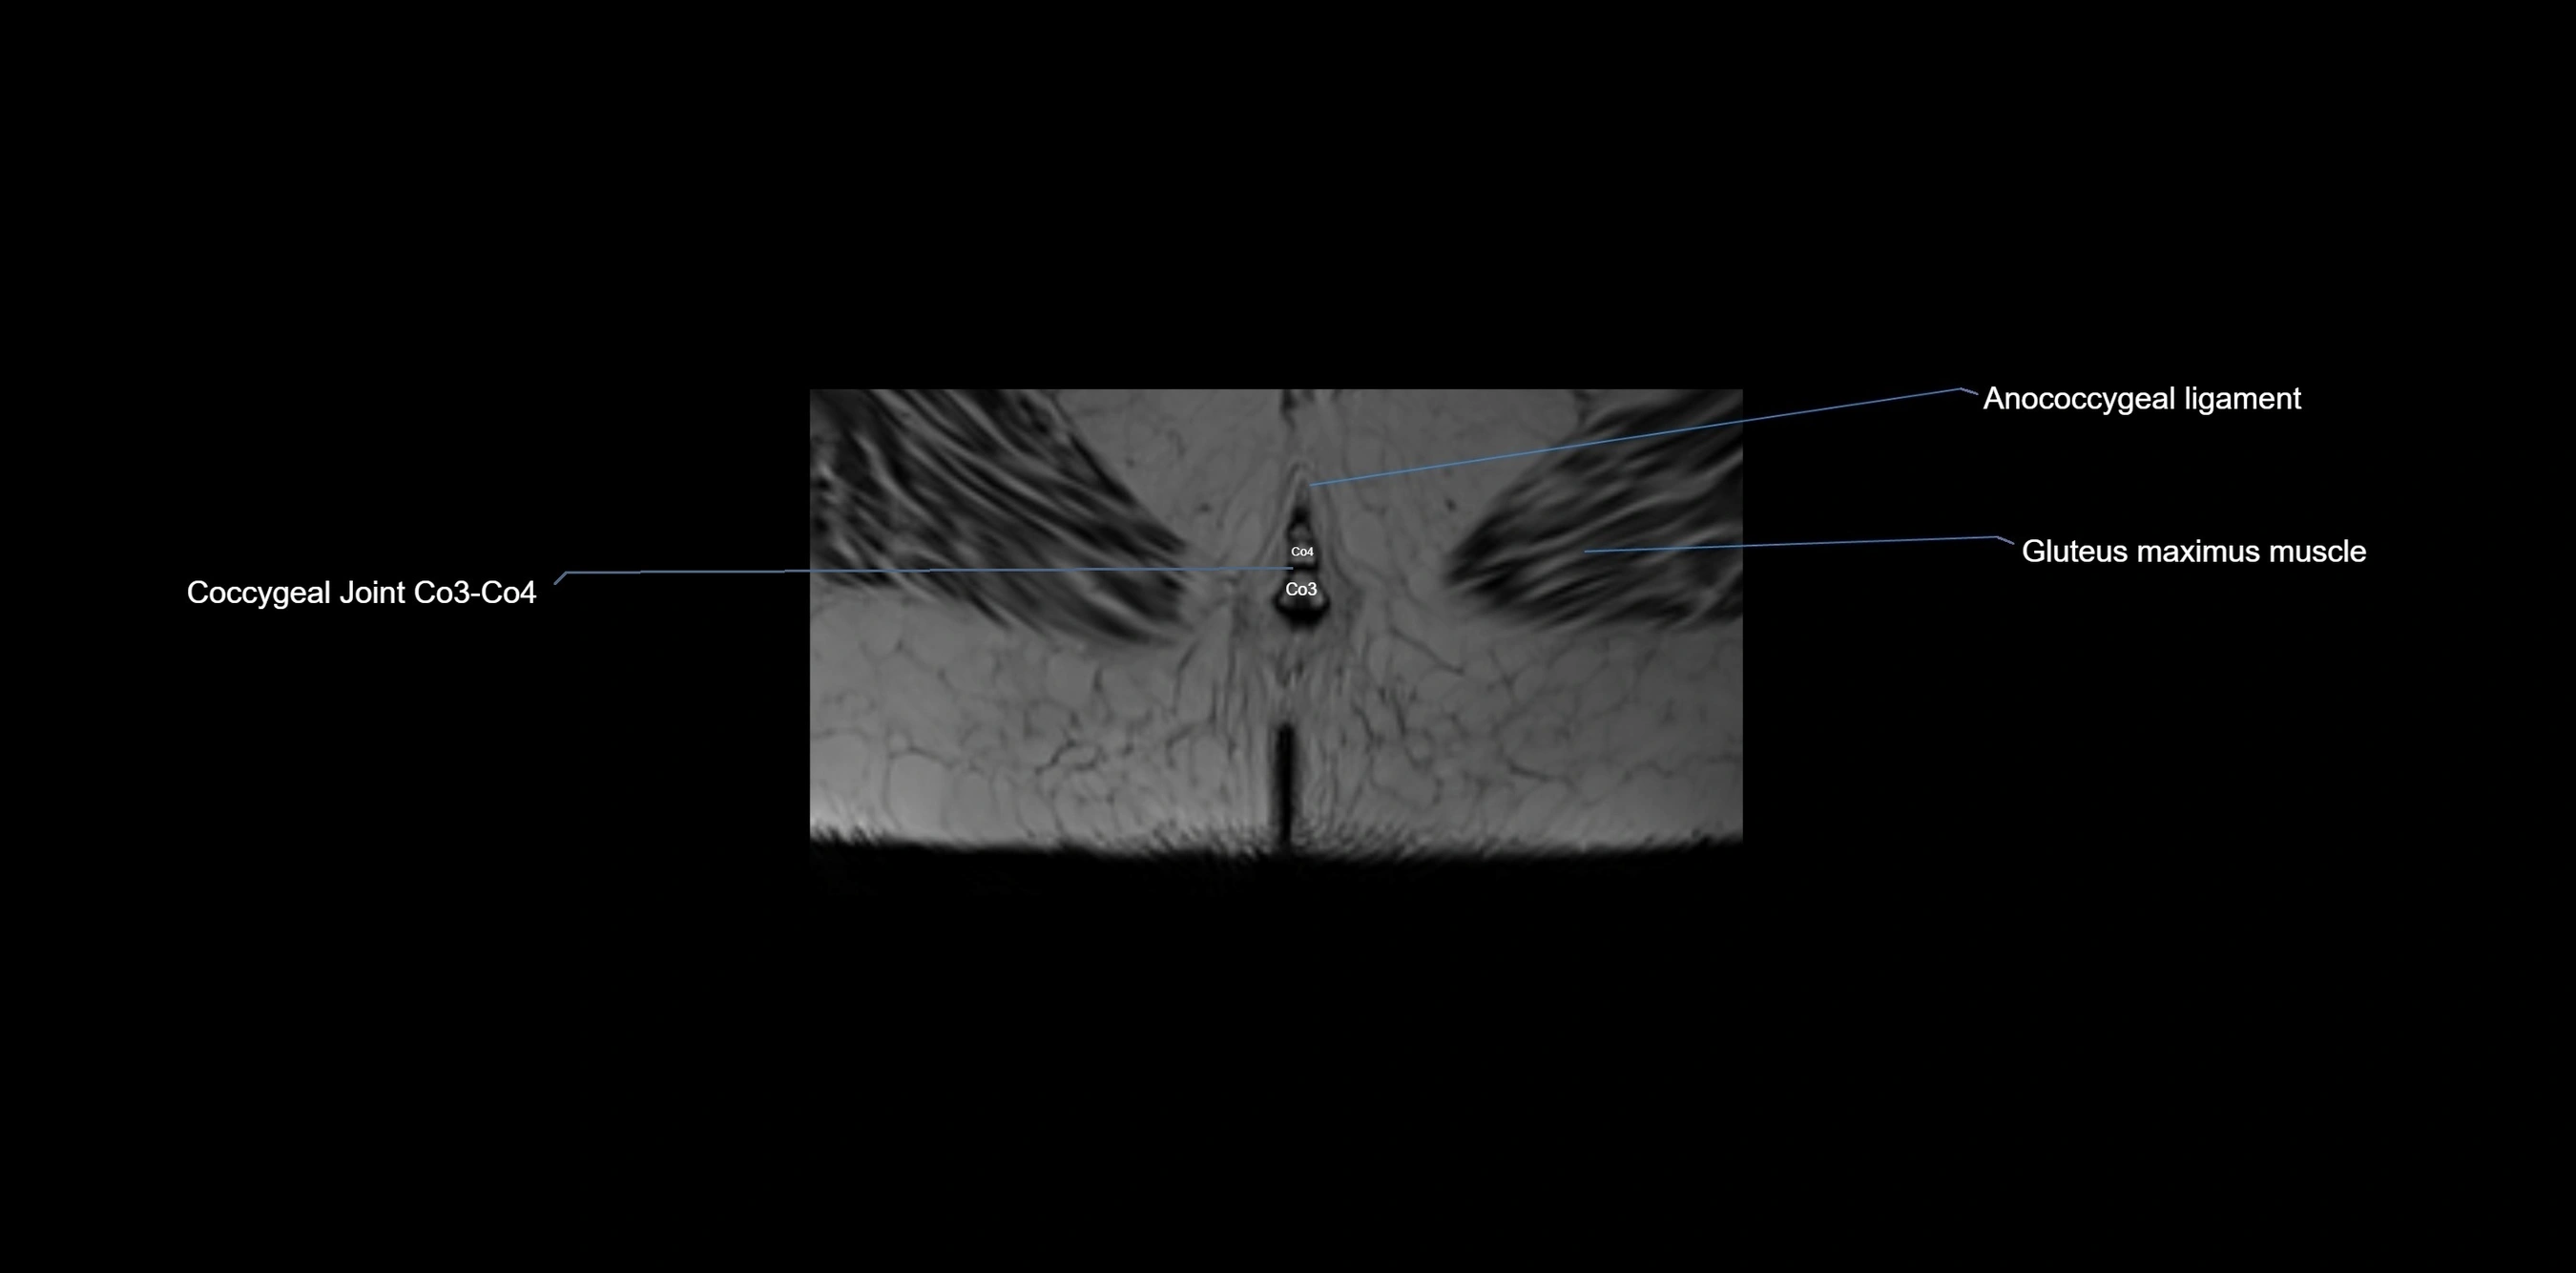

MRI Appearance

T1-weighted images:

• Cortical bone appears very low signal (dark); marrow shows intermediate signal

• Iliac fossa fat is bright against low-signal cortex

T2-weighted images:

• Cortical bone remains dark

• Marrow signal varies depending on fat content; edema or tumor shows hyperintensity

STIR:

• Suppresses fat, making bone marrow edema, fractures, or infiltrative lesions appear bright

• Excellent for trauma, sacroiliitis, and metastatic evaluation

T1 Fat-Saturated (Pre-contrast):

• Marrow: intermediate signal, fat suppressed

• Useful for detecting subtle marrow abnormalities adjacent to iliac cortex

T1 Fat-Saturated Post-Contrast (Gadolinium):

• Enhances vascularized structures, marrow pathology, tumors, and inflammatory changes

• Highlights soft tissue or bone invasion in pelvic neoplasms

MRI Non-Contrast 3D Imaging:

• Provides 3D morphology of iliac wing, crest, and articulations

• Used in preoperative planning for pelvic surgery and trauma reconstruction